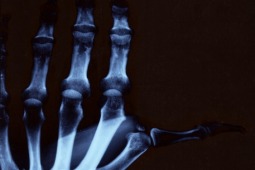

Reumatoidalne zapalenie stawów